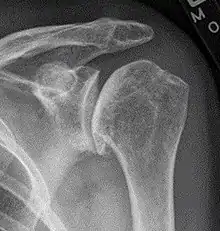

| Diagram of the human shoulder joint | |

The shoulder joint is composed of three bones: the clavicle (collarbone), the scapula (shoulder blade), and the humerus (upper arm bone) (see diagram). Two joints facilitate shoulder movement. The acromioclavicular (AC) joint is located between the acromion (part of the scapula that forms the highest point of the shoulder) and the clavicle. The glenohumeral joint, to which the term "shoulder joint" commonly refers, is a ball-and-socket joint that allows the arm to rotate in a circular fashion or to hinge out and up away from the body. The "ball" is the top, rounded portion of the upper arm bone or humerus; the "socket," or glenoid, is a dish-shaped part of the outer edge of the scapula into which the ball fits. Arm movement is further facilitated by the ability of the scapula itself to slide along the rib cage. The capsule is a soft tissue envelope that encircles the glenohumeral joint. It is lined by a thin, smooth synovial membrane.